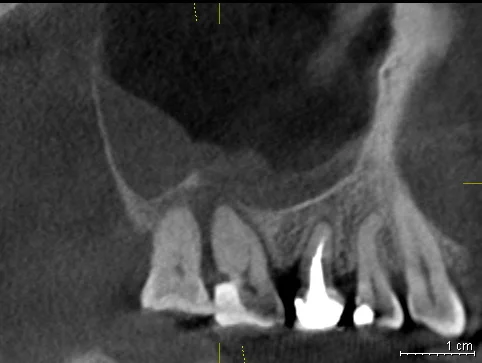

Давайте сравним снимки зубов, сделанные при помощи визиографа (слева), и при помощи компьютерной томографии (справа).

Как говорится, ощутите разницу. КТ - гораздо более точная и своевременная диагностика.